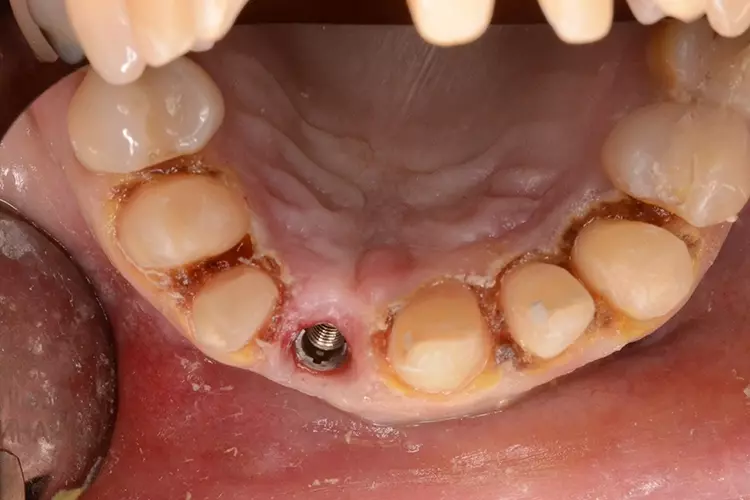

Bei dem heute 49-jährigen Patienten wurde seit Kindertagen versäumt, die Ober- und Unterkieferzahnbögen kieferorthopädisch auszurichten. Der Patient leidet seitdem stark unter seinen Zahnfehlstellungen.

Die Fraktur des stark elongierten Zahnes 21 war für den Patienten der Ausgangspunkt, sowohl die Front des Ober- als auch des Unterkiefers prothetisch überarbeiten zu lassen. Dabei wurde der frakturierte Zahn 21 durch ein navigiert eingesetztes Sofortimplantat ersetzt, während die verschachtelt stehenden Zähne 12 und 42 durch eine Brückenversorgung korrigiert wurden (Abb. 4a-j).